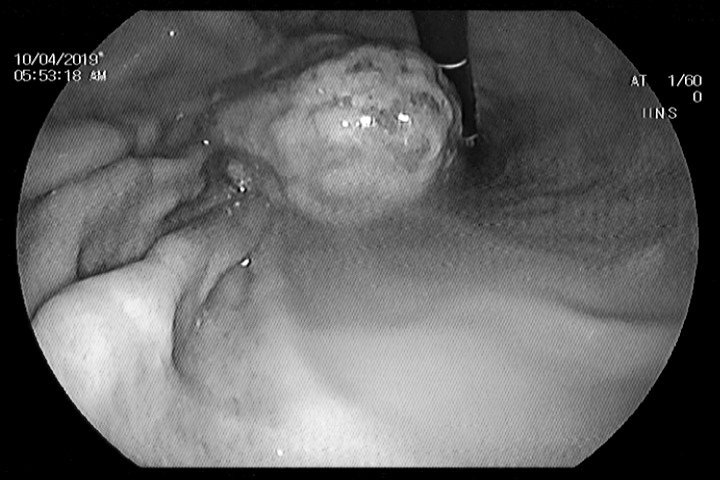

Hình ảnh nội soi khối bã trong dạ dày bệnh nhân. (Ảnh: BVCC)

Trong quá trình nội soi, các bác sĩ thấy hình ảnh một khối bã thức ăn màu vàng, cứng, chắc, kích thước 3x4cm trong dạ dày bệnh nhân.

Đây chính là nguyên nhân xuất hiện ổ loét kích thước khoảng 1cm nằm ở bờ cong nhỏ dạ dày bệnh nhân, khiến niêm mạc dạ dày vùng hang vị bị phù nề, xung huyết.